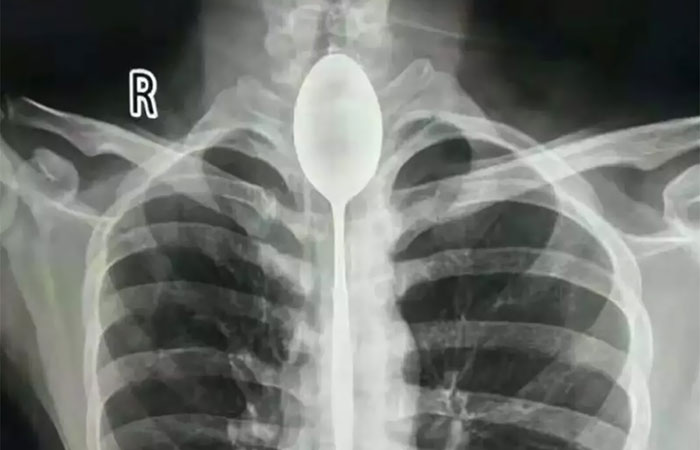

A Man In China Had A Steel Spoon Lodged In His Esophagus For A Year, But Surprisingly, The Half-Swallowed Utensil Didn’t Cause Too Much Discomfort